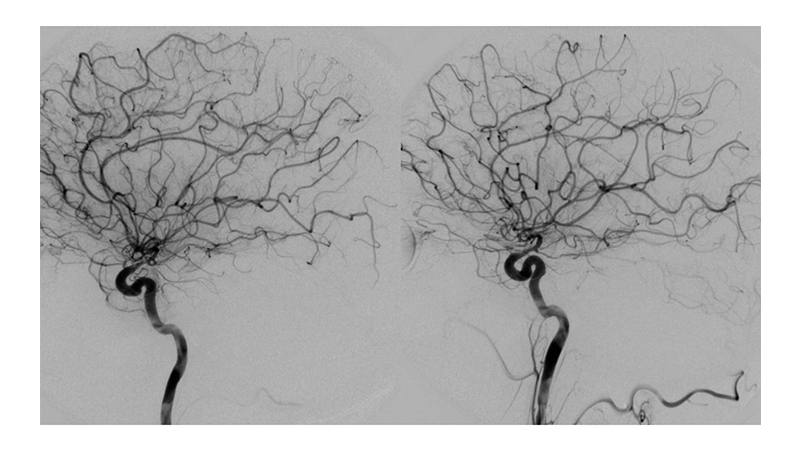

Εικόνα 6, 7, 8: Πλήρης απόφραξη του ανευρύσματος με coils. Ταυτόχρονα η αγγειοπλαστική του ανωτέρου τριτημορίου της βασικής αρτηρίας και των οπισθίων εγκεφαλικών έχει αποκαταστήσει την ροή αμφοτερόπλευρα.

Βλέπουμε την αποκατάσταση της διαμέτρου των οπισθίων εγκεφαλικών αρτηριών αλλά και της βασικής αρτηρίας, που έχει ως αποτέλεσμα την βελτίωση της παρεγχυματογραφίας του σπονδυλοβασικού συστήματος.